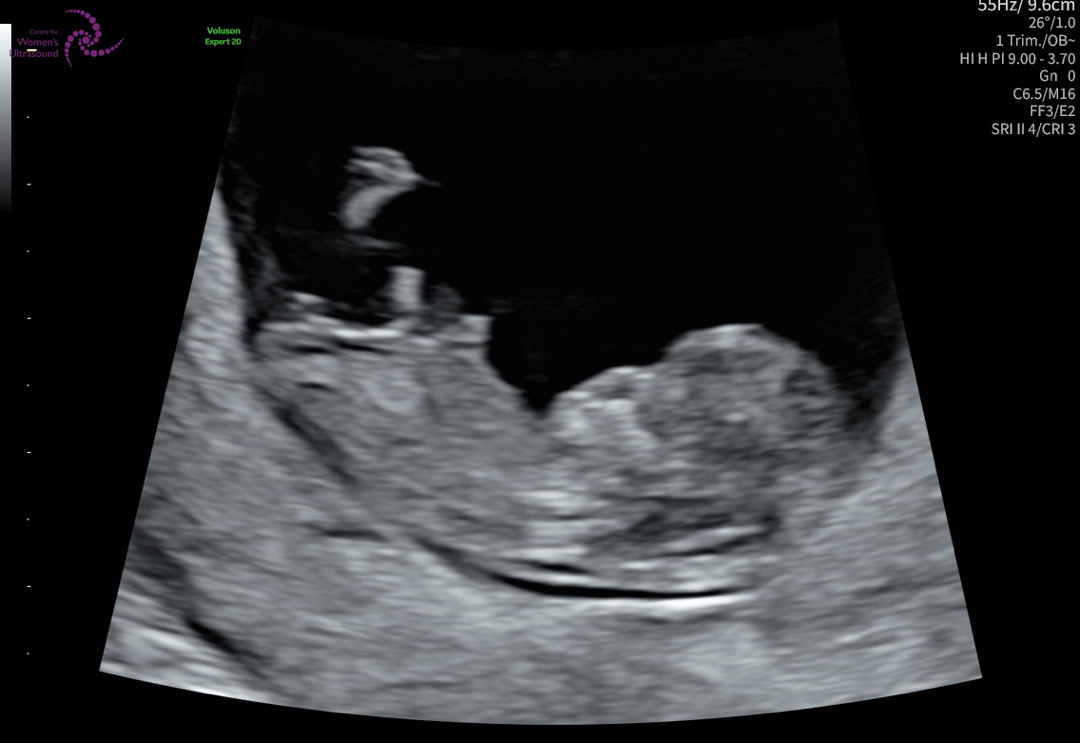

10주 6일 초음파 니프티 검사완료

으앙 너무 귀여워요ㅠㅠ 어떻게 이렇게 3주만에 사람형태가된건지 믿기지않네요..성별 기대되네요